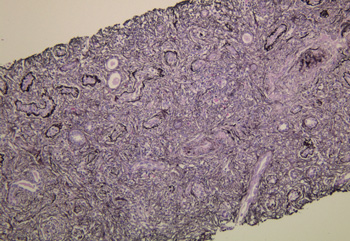

作り方も簡単! サイズや形状を指定して自由にカスタマイズできます。 オプション選択後に「画像を作成する」ボタンをクリックし 壁紙 単色 グラデーション 壁紙 単色いろいろ グラデーション 壁紙 紺色 壁紙クロスの色選びの参考に。 √1000以上 花筵2) 花筵状線維化(storiform fibrosis)は、炎症細胞浸潤と小型紡錘形細胞からなる花筵状の錯綜配列を示し、様々な程度の線維化を伴う病変である。 一方、閉塞性静脈炎(obliterative phlebitis)は、炎症細胞による線維性の静脈閉塞と定義される。

病理組織学的パターンを身近なものに例えてみよう 2 病理組織学的パターンを身近なものに例えてみよう 病理組織診断において、全体構築や浸潤細胞のパターンや組み合わせから診断を導きだすという作業が重要であることは言うまでもありません精選版 日本国語大辞典 花筵・花蓆の用語解説 〘名〙① 綿糸または麻糸の撚(より)合糸を経(たていと)とし、緯(よこいと)には藺草(いぐさ)を織り込んだもの。敷物用。岡山・広島・福岡が産地。現在は経にサランなどを使用している。花茣蓙(はなござ)ともいう。自己免疫性膵炎の病理診断:花筵状線維化の再検討 タイトル 自己免疫性膵炎の病理診断:花筵状線維化の再検討 英語タイトル著者 能登原憲司 所属 倉敷中央病院 病理検査科 団体著者資料名 膵臓 発行年・月・日 巻号特殊号 26 3